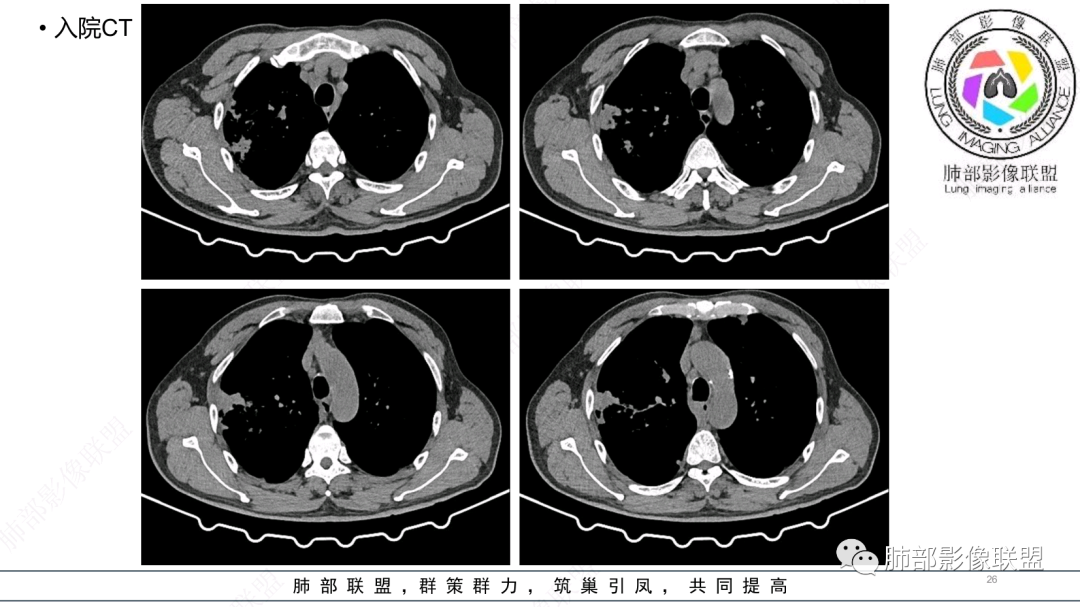

中老年男性,发病一周,发热,炎症指标明显增高,双肺支气管扩张基础,双肺可见多发结节、斑片状、团块状密度增高,边缘尚清。病灶分布与支气管关系密切,考虑支扩合并感染,铜绿,NTM、奴卡、曲霉等,环卫工人,可能接触腐败物较多,考虑曲霉可能大,鉴别奴卡。

男性,56岁,清洁工,临床表现咳嗽咳痰发热。胸部影像:两肺散在斑片、结节及实变影,大部分沿气道分布,以下肺为著并伴发多发支气管扩张及囊腔影,实验室检查白细胞增高,考虑感染性病变,曲霉、铜绿及NTM。

56岁,工作性质:环卫工人。主诉:咳、痰、喘、发病一周。急性起病(或者慢病+AE),呼吸道感染症状。化验指标白细胞、中性、CRP明显升高。影像学显示多灶性,有柱状支扩,囊状支扩等结构肺病,责任细菌主要考虑铜绿假单胞菌,不排除合并其他细菌以阴杆为主;存在树芽影,发热,炎症沿支气管束分布,是否合并TB?真菌?;树芽伴发热支原体感染也要需要考虑进去;全肺多灶性炎症,部分病灶周围有晕,右上叶疑似反晕,内部疑似有丝,右下肺考虑存在粘液栓,加之环卫工工作性质,考虑霉菌,主要考虑曲霉。

两肺支扩,两肺沿支气管分布多发结节、树芽及团块,边缘模糊,部分支气管管壁增厚,考虑气道侵袭性曲霉菌,鉴别铜绿、奴卡、结核。

CT:双肺延支气管血管束分布斑片状、团块状、树芽状密度增高影,部分边界模糊,支气管扩张、部分管壁增厚。考虑气道吸入细菌性感染,铜绿假单孢?